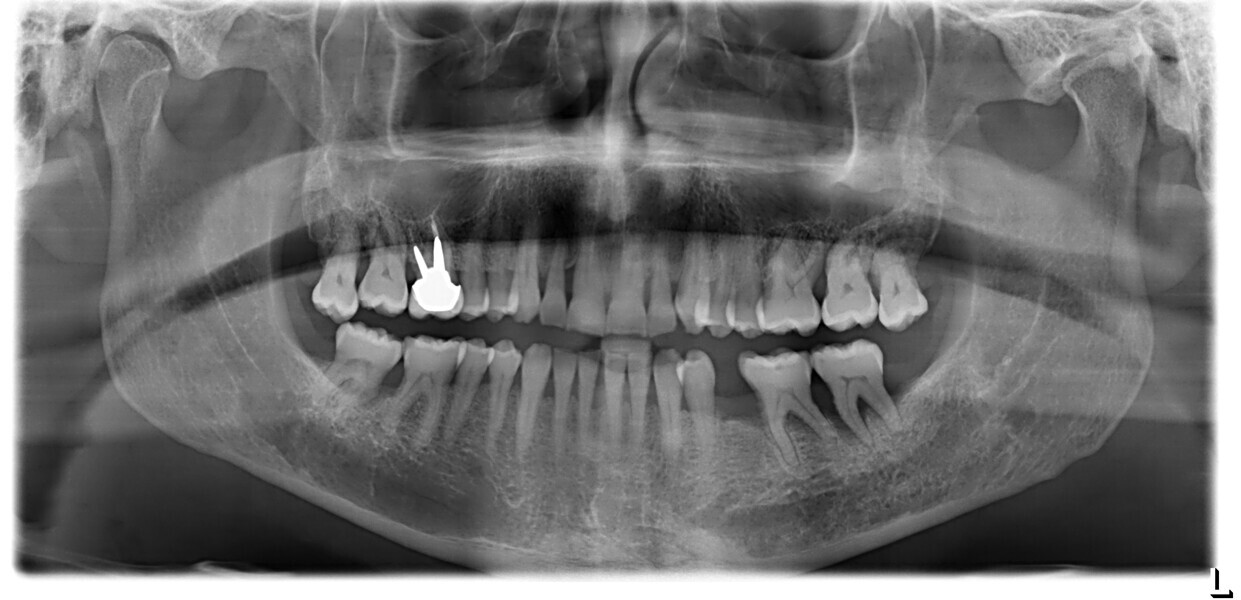

This patient, like all patients requiring interdisciplinary rehabilitation, had to first undergo periodontal treatment and caries restoration (Fig. 17). At the same time, it was important to rehabilitate swallowing with Froggymouth and relax the masticatory muscles and relieve the TMJs with an occlusal device. We could then study the orthodontic treatment plan using Invisalign ClinCheck (Align Technology) and showed the treatment plan to the interdisciplinary team and to the patient (Fig. 18). We were then able to create the correct sequence of orthodontic treatment, bone augmentation and implant surgery needed for the posterior edentulous spaces.

After the first phase of aligner treatment, we had achieved better inter-arch coherence, better maxillary arch expansion, and some space for improving the anterior tooth proportions restoratively (Fig. 19). We then temporarily restored the anterior teeth directly with composite, closing the spaces, improving the tooth proportions and further increasing the maxillary arch expansion (Fig. 20). We used restorative arch expansion to reduce the orthodontic destabilisation of the teeth to achieve the correct inter-arch coherence and retain the teeth in the cortical bone.38 A refinement aligner phase was undertaken to improve the final alignment of the gingival zenith and to improve the inter-arch coherence (Fig. 21). The periods of the first orthodontic phase and of the refinement were used to augment the mandibular and maxillary bone and to place the implants (Fig. 22). At the end of the orthodontic treatment, the case was finalised with ceramic veneers in the anterior area and temporary restorations on the implants in the posterior area (Figs. 23–26).

To monitor patient progress and the biological situation over time, we conducted periodic examination using radiographs and clinical assessment. Additionally, we evaluated the functional behaviour of the tongue and mastication using the swallowing analysis mentioned earlier and the G-test (chewing gum mastication test; Fig. 32).26